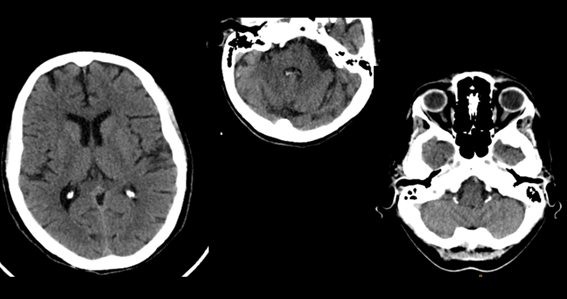

Encontramos como primer error el volumen parcial dado por estructuras vecinas, es frecuente con las estructuras óseas

Los lóbulos temporales y fosa posterior son afectados por artefactos de endurecimiento del rayo y se aprecian como zonas de hipodensidad irregular y no debe confundirse con gliomas. Se diferencian por la falta de masa.

Fig. 10.

Fig. 9.